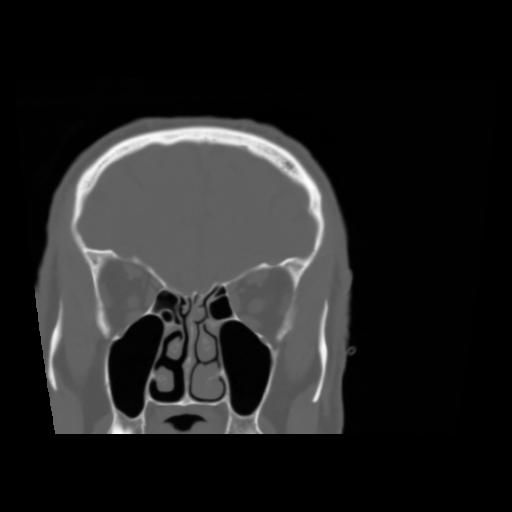

5 CEREBRO,,Coronal,3.000,CEREBRO,Coronal,